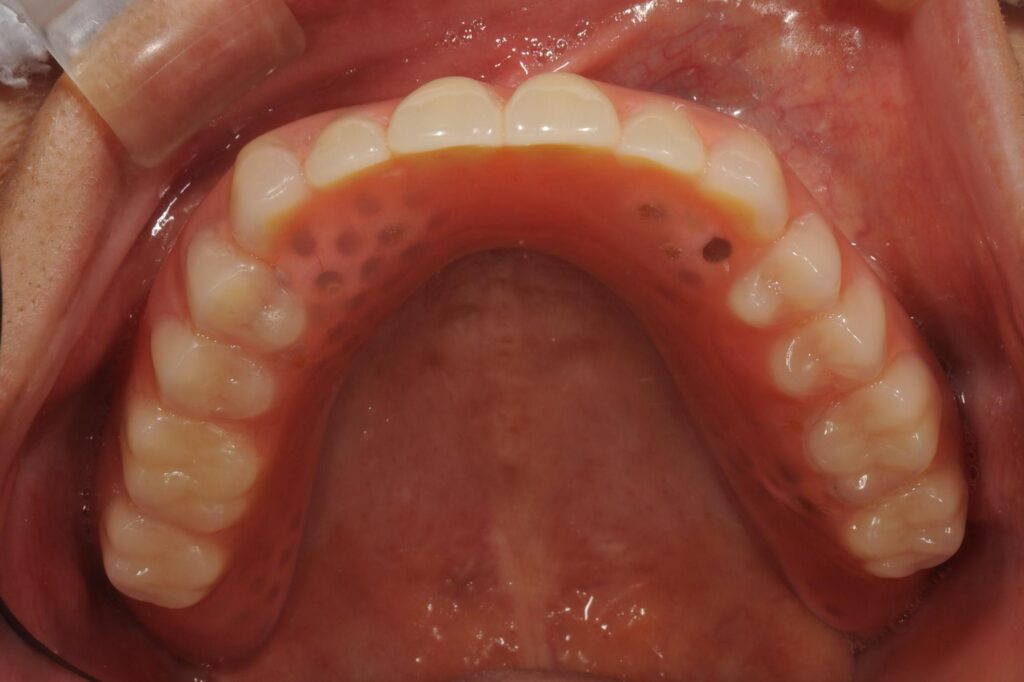

最終的にはどのような状態になるのか、他の方の写真でお伝えします。

【最終のお口の様子(上記患者様ではありません)】

このような状態になります。

ここで、上顎の状態ですが、以下に詳細を記載します。

結論は、入れ歯なら取り外し可能なのでものすごく歯磨きしやすいですよ!

実際の写真を見て下さい。

いかがでしょうか。

インプラントで固定式の物も、もちろんメリットはたくさんあると思います。ただ、このように入れ歯なら外せることで、いつでも綺麗な状態をキープしやすい、つまり虫歯や歯周病に罹患しにくくなることで、長持ちするという結論です。